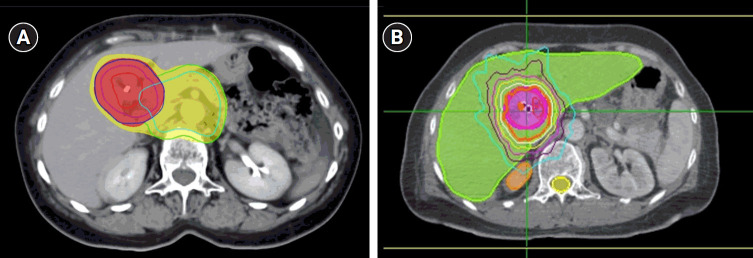

Purpose: For patients with unresectable extrahepatic cholangiocarcinoma, radiotherapy (RT) is the definitive treatment. In this study, we aimed to evaluate the role of two different RT techniques for definitive treatment of unresectable extrahepatic cholangiocarcinoma.

Materials and methods: Eighteen patients with unresectable extrahepatic cholangiocarcinoma treated with either conventionally fractionated radiotherapy (CFRT) or stereotactic body radiotherapy (SBRT) were evaluated retrospectively. Patients treated with CFRT also received elective nodal irradiation (ENI) in addition to the primary tumor.